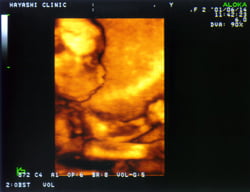

妊婦健診時に3D超音波を行っています

妊婦健診の超音波測定で、赤ちゃんの様子がわかる3D超音波を行っています。

実際の写真(大きさは異なります)

写真には上図のような顔が写っています。

胎位により、3D画像がうつりにくい場合がありますので、週数時期については、技師にお任せください。